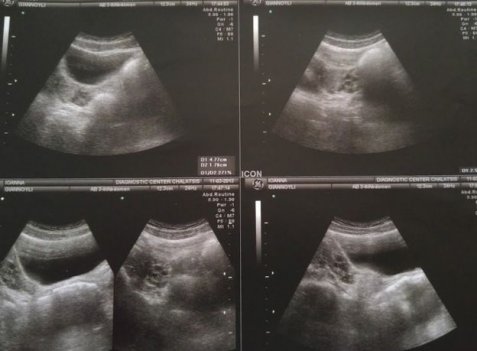

Ο κολπικός υπέρηχος της Ιωάννας το 2013